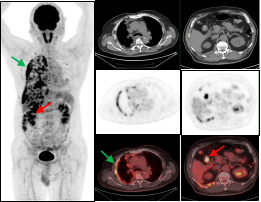

鼻咽癌全身转移:PET/CT显像示鼻咽左侧高代谢软组织肿块(绿色箭头);病理证实鼻咽非角化上皮癌,双侧颈部、肝脏及双侧髂骨多发转移瘤(红色箭头)。

胰腺癌全身转移:胰腺体尾部胰腺癌(绿色箭头),肝脏多发转移瘤及胸9椎体转移瘤(红色箭头)。

双癌检出:通过PET/CT一站式检查,同时检出两种肿瘤:甲状腺癌(绿色箭头)及子宫内膜癌(红色箭头),有利于临床治疗方案选择。

图A绿色箭头示右侧胸膜多发转移,图B红色箭头示结肠肝曲局部管壁稍厚形成软组织灶,糖代谢增高,肠镜证实结肠肝曲腺癌。